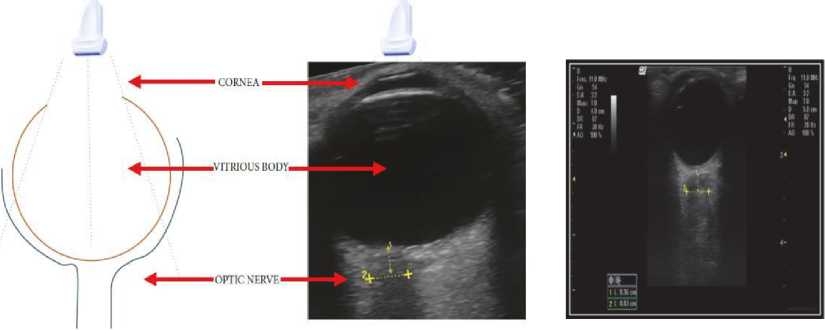

Gambar 1 : USG anatomi dari bulbus oculi dan selubung saraf optikus pada potonganaxial dan sagital dikutip dari Jimenez Restrepo, 2019

Gambar 2 : Teknik pengukur diameter selubung saraf optikus dengan USG pada posisi a. transbulbar lateral dan b. anterior transbulbar. Gambaran USG yang didapat c. lateral transbulbar dan d. ultrasonografi transbulbar Dikutip dari Hall M 2013